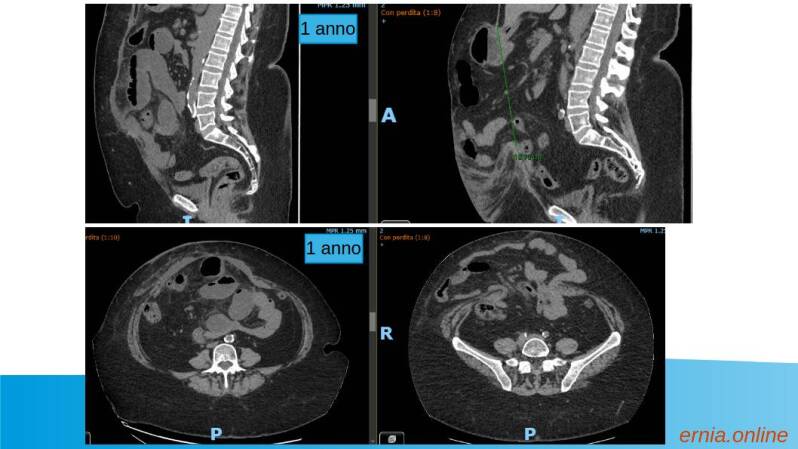

LAPAROCELE W3, controllo a 1 anno

LAPAROCELE W3 , controllo a 1 anno TAC